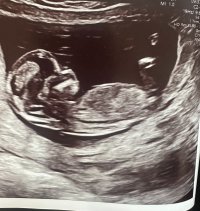

Vil dere gjette ut fra teorien hva kjønnet kan være? blir litt gal og sykehuset ville ikke si det fordi det var for tidlig..

nå har jeg fått bekreftet om at det er liten jenteHar disse ogsåhåper man kan se det på et av bildene hvertfall (alle de er tatt samme dag 12+3) @lyse gul